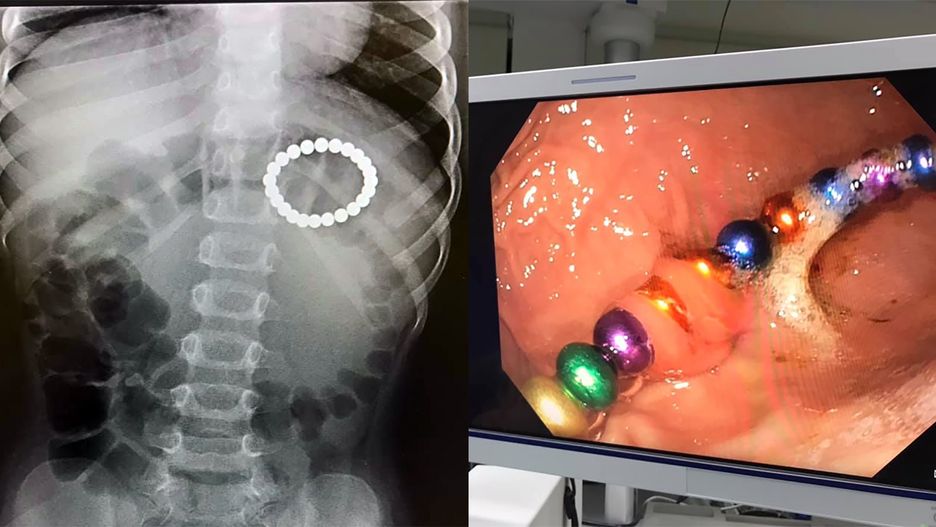

Lekarka Magdalena Dobrowolska opublikowała w niedzielę w mediach społecznościowych zdjęcia kolorowych, metalowych kulek, które trzeba było usunąć z brzucha małego pacjenta. Post udostępniło ponad 10 tys. osób. Okazuje się, że zabawka może być bardzo niebezpieczna.

Tym razem udało je się usunąć metodą gastroskopii i dziecko nie potrzebowało operacji – napisała lekarka.

Kulki nie zrobiły "dziury" w przewodzie pokarmowym dziecka, ale gdyby poleżały tam jeszcze kilka dni to pewnie by tak się stało. Nie ma tygodnia, żeby do nas do szpital nie trafiło dziecko, które zjadło magnesowe kulki – stwierdziła lekarka.

Do uszkodzeń narządów wewnętrznych dziecka może dojść ze względu na to, że kulki są magnetyczne. Jak tłumaczą lekarze, mogą one zwierać się przez ściany przewodu pokarmowego i powodować niedrożności. Na szczęście nie zawsze konieczna jest pełna operacja, w niektórych wypadkach kulki udaje się usunąć podczas zabiegów endoskopowych.